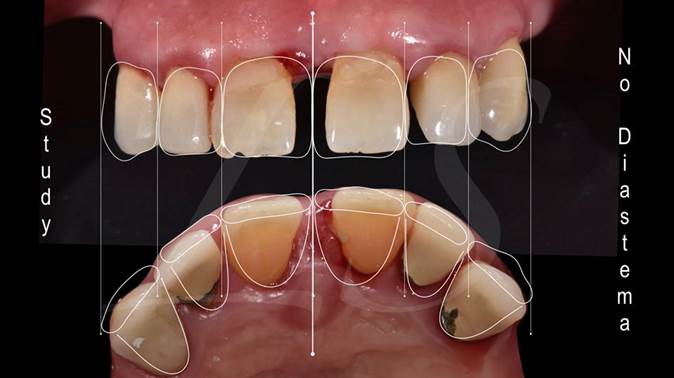

Clinical case: AnyRidge immediate loading

- Courtesy of Dr. Andres Paraud Freixas, Chile -

AnyRidge, ISQ value, initial stability, immediate loading, KnifeThread, maxillary anterior, Mega ISQ, Dr. Andres Paraud Freixas

AnyRidge implant system, Mega ISQ, Digital prosthesis

“Patient’s smile was recovered on the day of surgery

with reliable & highly-aesthetic results using AnyRidge & R2GATE. ”